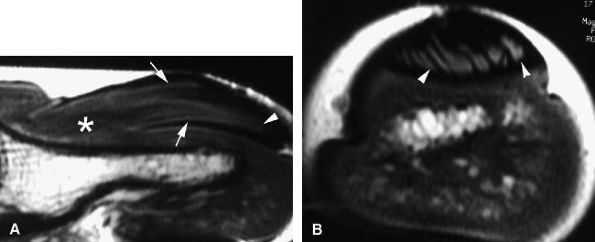

|

FIGURE 11.47 ● Jersey finger. (A) Sagittal T2-weighted image. (B) Coronal post-contrast T1-weighted images. (C) Axial T1-weighted image. Distal avulsion of the FDP tendon is shown with the proximal end (white arrows) at the metacarpophalangeal joint (type I). The tendon is wavy in the palm (arrowheads). The empty digital canal (in C) may mimic a remnant tendon, but the FDS tendon (asterisk) is alone in the canal.